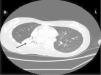

Case reportA female patient with a congenital muscular dystrophy had been treated with nocturnal nasal noninvasive positive pressure ventilation (NIV) since she was 20. At the age of 26 she was hospitalised for a complete atelectasis of the right lower lobe, and had recovered after more than a month with the application of an intensive combined protocol of HFCWO (The Vest Airway Clearance System, Hill-Rom St. Paul, MN, USA) plus manual and mechanical assist cough (In-Exsufflator, Cough-Assist®, Philips Respironics, Murrysville, PA, USA). Her clinical condition remained good until the age of 28, when her lung function tests showed the following values: vital capacity 0.55 L (16% of the predicted value), maximal inspiratory pressure 10cmH2O (11% of predicted), maximal expiratory pressure 14cmH2O (13% of predicted), and peak cough expiratory flow 80L/min. A few months later, due to the appearance of fever and copious mucus production, she was treated with manual and mechanical chest physiotherapy plus antibiotics (ceftriaxone) initially. However, she still complained of dyspnea and a feeling of retained secretions, and was then admitted to hospital. She had a severe left convex scoliosis with a mean Cobb angle of over 70°. After a chest X-ray, a CT scan was performed (Fig. 1) which showed atelectasis of the right lower lobe. Her diurnal arterial oxygen saturation (SpO2) fluctuated between 82 and 85% in room air, while PaCO2 was normal. The patients showed minimal clinical signs of dehydration, namely dry mouth. She had good skin turgor and normal urine output. Haematocrit and electrolytes were normal except for potassium which was lower than normal. We began nutritional support and hydration because the patient was not able to eat and drink enough. Negative results were obtained from sputum cultures; however, intravenous antibiotics were administered. Twenty-four-hour NIV was begun, with the addition of oxygen (5L/min), as NIV alone was not enough to maintain SpO2 above 90%. Fifteen-twenty minutes sessions of HFCWO at a pressure of 5cm H2O and a frequency of 12Hz were performed; each session was followed by five or six sessions of mechanical assist cough with an In-Exsufflator at pressures of +40/−45cm H2O, delivered respectively over 3 and over 2s, with an abdominal thrust timed to the exsufflation cycle. This protocol was applied 4 times/day; additionally, In-Exsufflator was used on demand. Once 24-h NIV had begun, we asked the patient to frequently change her decubitus. However, as she had a severe scoliosis, she hardly changed her body position tending to remain on her right side. As the patient demonstrated a modest clinical improvement, we hypothesized that bronchial secretions had a high concentration of DNA due to accumulation of degenerated leukocytes. Therefore, one week after admission we tested rhDNase (Pulmozyme®; Roche, Basel, Switzerland). For three days, 2.5mg were delivered twice daily with a jet nebulizer, using an in-line nebulizer with NIV, without success. The next day flexible fiberoptic bronchoscopy (FOB) was performed, during NIV plus oxygen, to get a better evaluation of the cause of the obstruction and to possibly instill rhDNase bronchoscopically. FOB showed a lot of very thick mucus in the lower right lobe, but, due to its high viscosity, only a small amount could be removed. Then, a single dose of 2.5mg rhDNase was instilled directly over the affected area. As the procedure was performed in a clinical ward and the patient was at risk of intubation, this was carried out together with an Intensivist. Anyway, we had no complications except for a mild transient decrease in SpO2. The patient was closely monitored by trained nurses. Copious but thinner secretions were removed with the help of the In-Exsufflator. It had to be used six times in the first hour and three times in the second hour for periods lasting from 1 to 2min to 10 or more consecutive minutes. In the following hours the In-Exsufflator was applied only according to the protocol and within 24h a significant clinical improvement was evident, with a reduced need of oxygen. A new CT scan demonstrated a significant reduction of the atelectatic area (Fig. 2). The treatment was repeated two days after the first instillation with the same dose of the drug, with a further clinical improvement that allowed us to withdraw oxygen. Even after the second instillation, MI-E was often required, four times in the first hour and once in the second hour, unlike in the following days when it was applied only according the protocol. Two days later the patient was discharged (Table 1). A month later the clinical and radiological recovery was confirmed (Fig. 3).